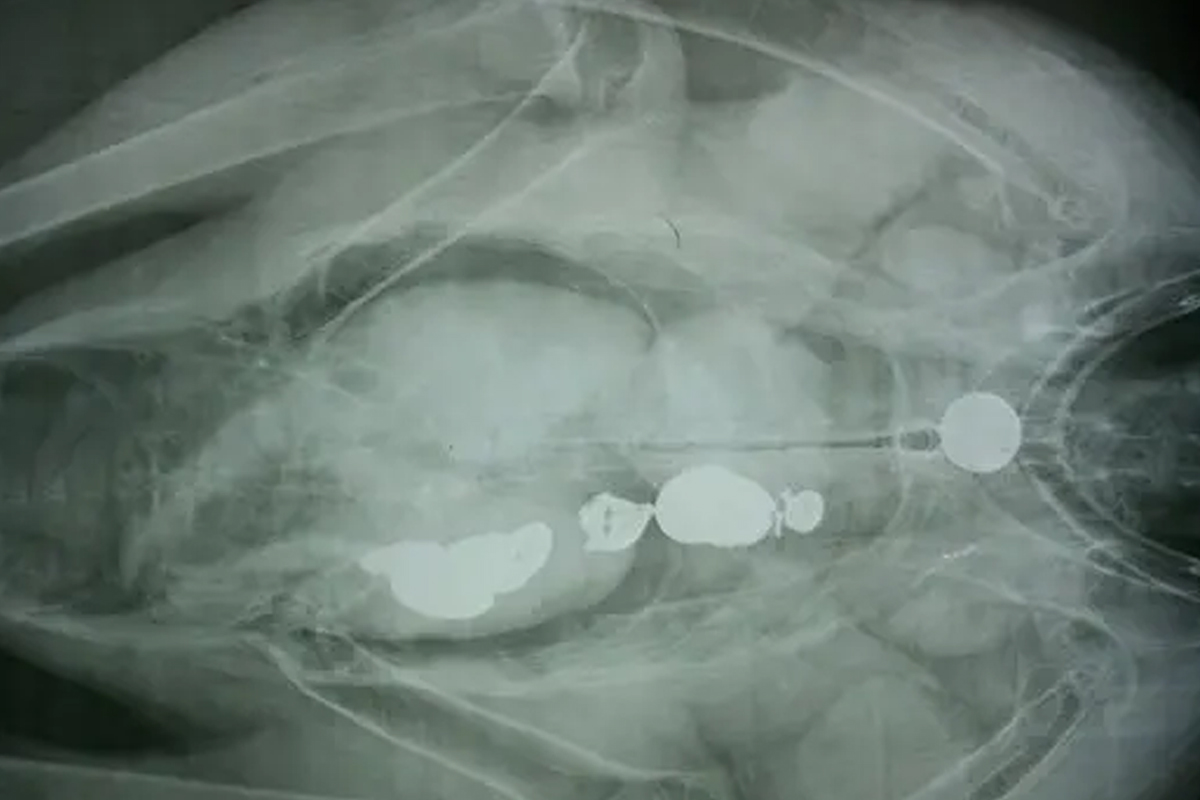

이들은 쓰레기 투기의 위험성을 알리고자 콘도르 뱃속을 촬영한 엑스(X)선 사진 결과를 공유하기도 했습니다. 해당 사진의 콘도르 몸속에는 관광객들이 던진 열쇠와 동전이 가득했죠.